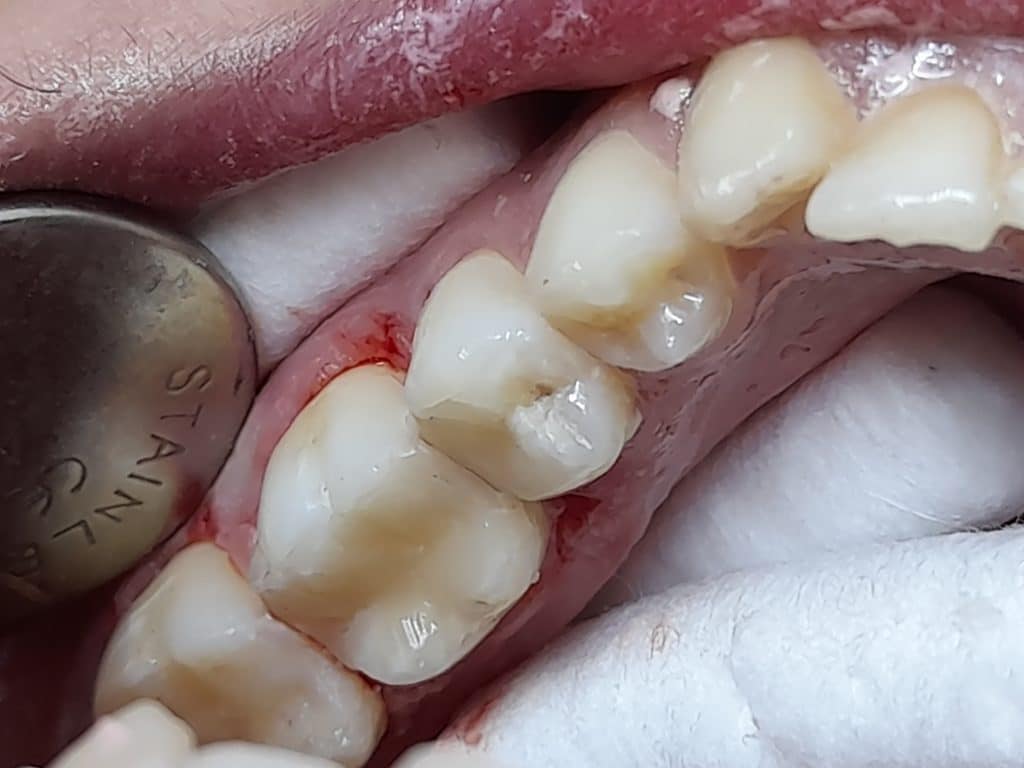

Cold test, clinical examination and Radiographs for diagnosis

Tooth 35 diagnosis: irreversible pulpitis

Tooth 36 diagnosis: necrotic pulp and acute apical periodontitis